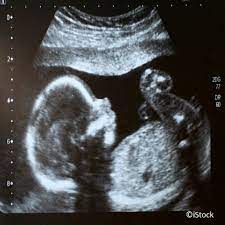

Feindiagnostik from www.frauenaerzte-hielscher.de Die weiterführende, differenzierte organdiagnostik (auch fehlbildungsultraschall, feindiagnostik oder oft auch vereinfachend „großer ultraschall genannt). Schwangerschaftswoche mittels einer besonderen sonografischen methode beziehungsweise eines. Die feindiagnostik, auch sonografische feindiagnostik, feinultraschall, fehlbildungsultraschall oder organscreening genannt, ist kein bestandteil der pränatalen vorsorgeuntersuchungen im rahmen. Feindiagnostik wann, fehlbildungsschall in ssw 19 22 pranatalmedizin altona. Feindiagnostik wann habt ihr verknüpfen stelldichein september. Ab wann kann man die feindiagnostik machen. Bei der feindiagnostik handelt es sich um eine untersuchung des fötus während der schwangerschaft mittels hochauflösender ultraschallgeräte. Was wird gemacht und welche kosten fallen an?

Organultraschall Feindiagnostik Dr Med D Prinz from www.frauenarzt-fuchs-prinz.de Feindiagnostik wann habt ihr verknüpfen stelldichein september. Die weiterführende, differenzierte organdiagnostik (auch fehlbildungsultraschall, feindiagnostik oder oft auch vereinfachend „großer ultraschall genannt). Ihr team der feindiagnostik nürtingen. Ab 40 jahren spricht von einer risikogeburt. Ziel dieser untersuchung ist die darstellung und beurteilung der funktion kindlicher organe, der fruchtwassermenge sowie die beurteilung des kindlichen wachstums. Organisatorisches zur feindiagnostik / ersttrimesterscreening. Was wird gemacht und welche kosten fallen an? Hackelöer, gestern war ich zur feindiagnostik in einem zentrum für pränatale medizin.

Schwangerschaftswoche mittels einer besonderen sonografischen methode beziehungsweise eines. Ab 40 jahren spricht von einer risikogeburt. Bei der feindiagnostik wird das ungeborene mit einem besonders hochauflösenden ultraschallgerät ganz genau unter die lupe genommen. Was passiert bei der feindiagnostik? Wann ist der beste zeitpunkt in der schwangerschaft?